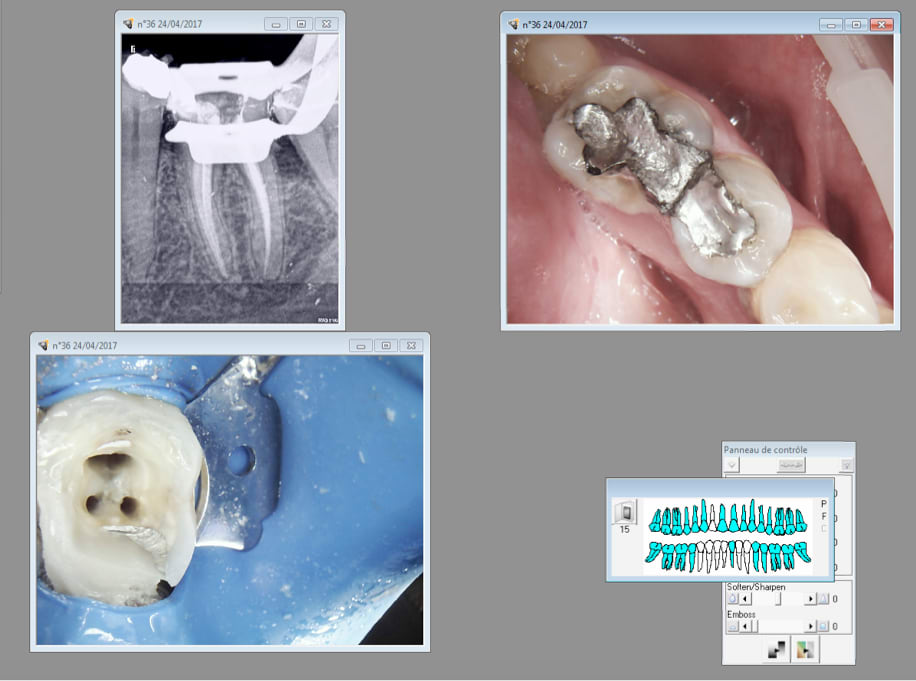

J'ai l'impression que mon joypex 5 commence à merder. Du coup j'essaye celui ci qui marche à merveille. -)

J'aime pas finir des soins que je n'ai pas commencé. A votre avis perfo distale ou carie pré existante ? -)

Le patient se plaignait depuis longtemps d'une douleur niveau 26 27 avec pèche ca m'étonnerait que 16 ( je pense intacte au début) en soit la cause car il y a une image sur la racine mésiale de 17. Fracturée ou MV2 non traité ? Bizarre bizarre.

Ah oui le canal palatin était vivant.

Je penche plus pour un problème paro ...

Fêlure de 16, perte osseuse et douleur qui engendre une complication endo- paro sur 17...

la photo revele clairemen une felure bien infiltrée

que donne le sondage ?

Pas fait de sondage. La 16 donnant des signes de sensibilité à la percussion j'ai fait l'endo. On verra pour le sondage après. -)

Mais peut etre que le sondage a été fait à la lime 15 par la perfo en distal de 16. Je n'ai pas de compte rendu pour savoir ce que ca a donné. Je ne sais pas si tu as remarqué mais la cavité d'accès est légèrement désaxée en distal. La dent en outre était vivante du moins le canal palatin. -)

4 endos molaires aujourd'hui. Réglé comme du papier à musique ce petit localisateur d'apex chinetoque. -)

Et encore une couronne sur dent vivante qui foire une ! -)

Ca a bien le temps de se calcifier avant de crever ca ne rend le chalenge de trouver le mv2 que plus intéressant. -)